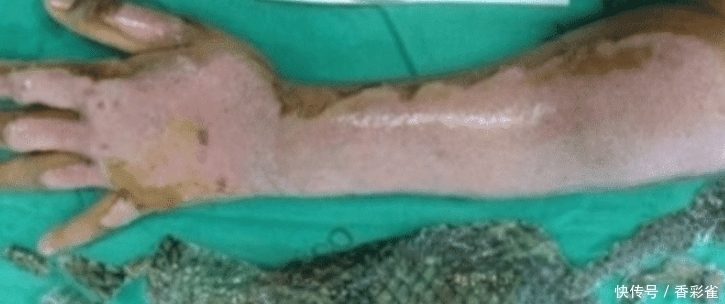

可以看到这样的形象一开始确实有点让人难以接受,就感觉是人兽的杂交一样。但是当这位巴西医生为女士植上了鱼皮之后,女士的情况都得到了好转。

【 痊愈|女子全身被烧伤,医生植入“鱼皮”痊愈,网友:能美白吗?】使用的这种鱼食罗非鱼,它的皮能够加速皮肤的生长,能够更有效的治疗。这种鱼食专门饲养出来的,然后由专业的人负责剥皮,然后放在一个特殊的容器中,以保持其活性。在人植入这种皮之后,经过几个星期的更换,皮肤就能完全好了。大家是不是觉得很诧异呢?